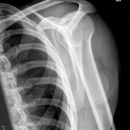

Schulterluxation